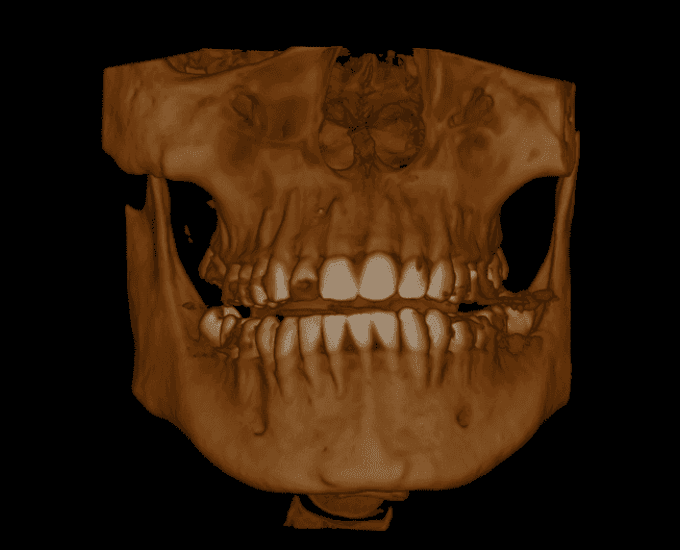

Any CT scans

Volume example 1 Volume example 2 Volume example 3 Volume example 4 Volume example 5 Volume example 6